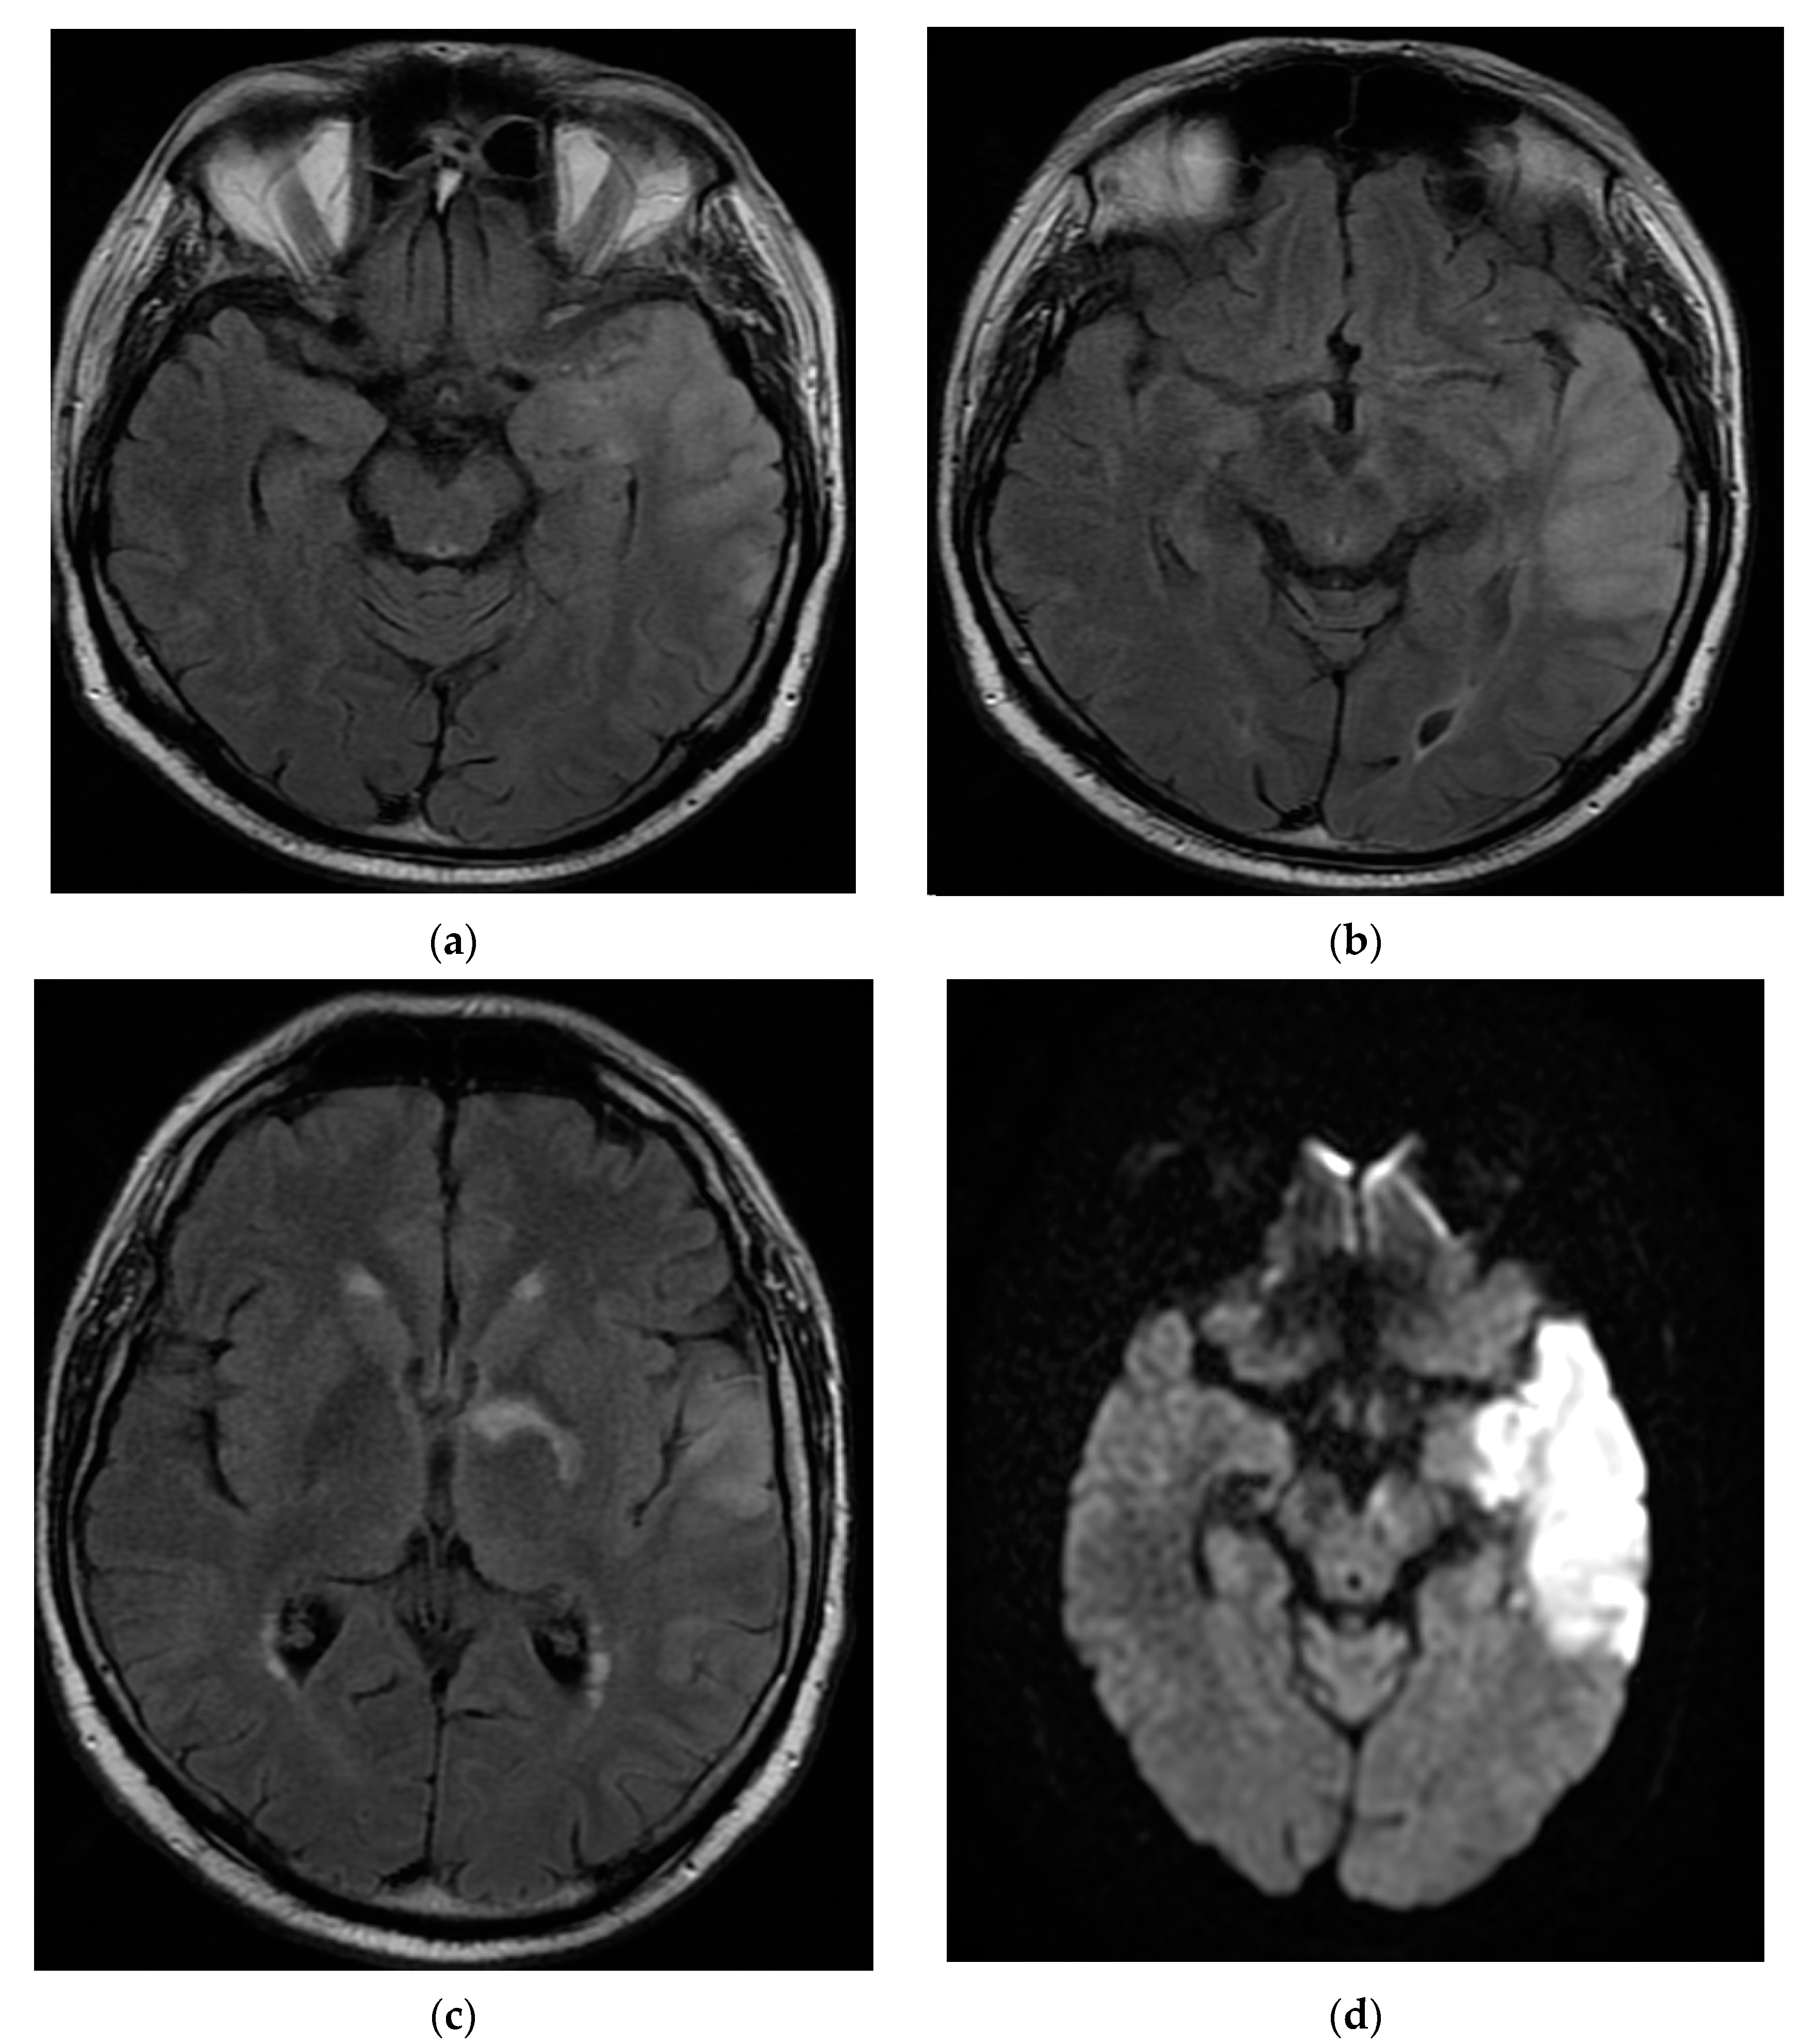

The patient returned after one month to the emergency department with right hemiparesis, mixed aphasia, incomplete left ophthalmoplegia, severe headache, and agitation, without fever. He was tested again for SARS-CoV-2 with nasal polymerase chain reaction (RT-PCR) and was found to be positive. His vitals were stable and non-contrast brain CT showed left capsulo-lenticular and temporal hypodensities. MRI brain images with and without contrast showed aspects in T2, Flair, and DWI hypersignal without contrast capture of the left temporal cortex, respectively, the hippocampal and ipsilateral parahippocampal region. An MRI brain scan also revealed multiple images in hypersignal T2, Flair, and DWI with dimensions of 2–10 mm located juxtacortically and deeply periventricular fronto-temporo-parietal bilateral. The appearance was suggestive of encephalitis (Figure 2).

Figure 2.

MRI brain images with contrast showed aspects of T2 axial Flair hypersignal in the left temporal lobe (a,b), respectively, in the hippocampal and parahippocampal region (c). The lesion is hyperintense on the DWI axial image (d). MRI: magnetic resonance imaging; Flair: fluid attenuated inversion recovery; DWI: diffusion weighted imaging.